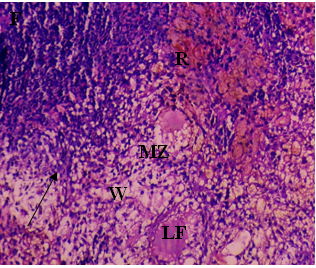

The current investigation focused on spleen histopathology to examine the overall condition of the organ. Elmore (2006), R. E. Mebius and G. Kraal (2005), as well as other sources, were used to anatomize the histopathological differences shown in fig. 114,15. Fig. 1 shows normal histoarchitecture in the control spleen tissue of a male albino rat, with sufficient amounts of red pulp (R), white pulp (W), lymphoid follicles (LF), and marginal zone (MZ). Table 2 has detailed histology observations. The histological structures in the cyphenothrin-treated group were well terminated, just like in the control group. The red pulp in the group that received high doses of the pesticide cyphenothrin showed decreased cellularity, while the white pulp was severely destroyed, with no normal lymphoid follicle and boundary zone. White pulp and red pulp from the low-cure cyphenothrin group showed destroyed cellular integrity. This cyphenothrin-treated group, which included high and low doses, demonstrated notable modifications of histological structures in contrast. In comparison to the cyphenothrin high dosage group, the white pulp recovered effectively in the cyphenothrin insecticide low dose treatment group.

Fig. 1: (A) and (B) Spleen sections of control rats: (R) red pulp; (W) white pulp; (LF) lymphoid follicle; (MZ) marginal zone; (PALS) Periarteriolar lymphoid sheath. H and E, x100. (C) and (D) Spleen structure of rat treated with cyphenothrin (63.6 mg/Kg BW) respectively: arrow head Show a thin damaged marginal zone (MZ), asterisk (*) indicates decreased cellularity (rarefication) and altered structural integrity of white pulp, H and E, 100×. (E) and (F) spleen tissues of cyphenothrin treated (35.33 mg/Kg BW) respectively: arrow shows damaged tissue region, marginal zone (MZ) and lymphoid follicles (LF). H and E, 100